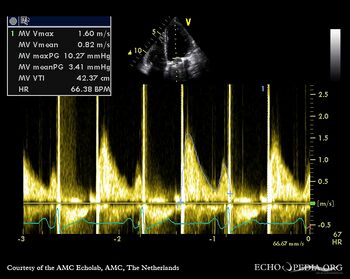

E00602.gif

E00603.jpg

A4CH with Color Doppler Continuous-wave Doppler signal of transmitral flow